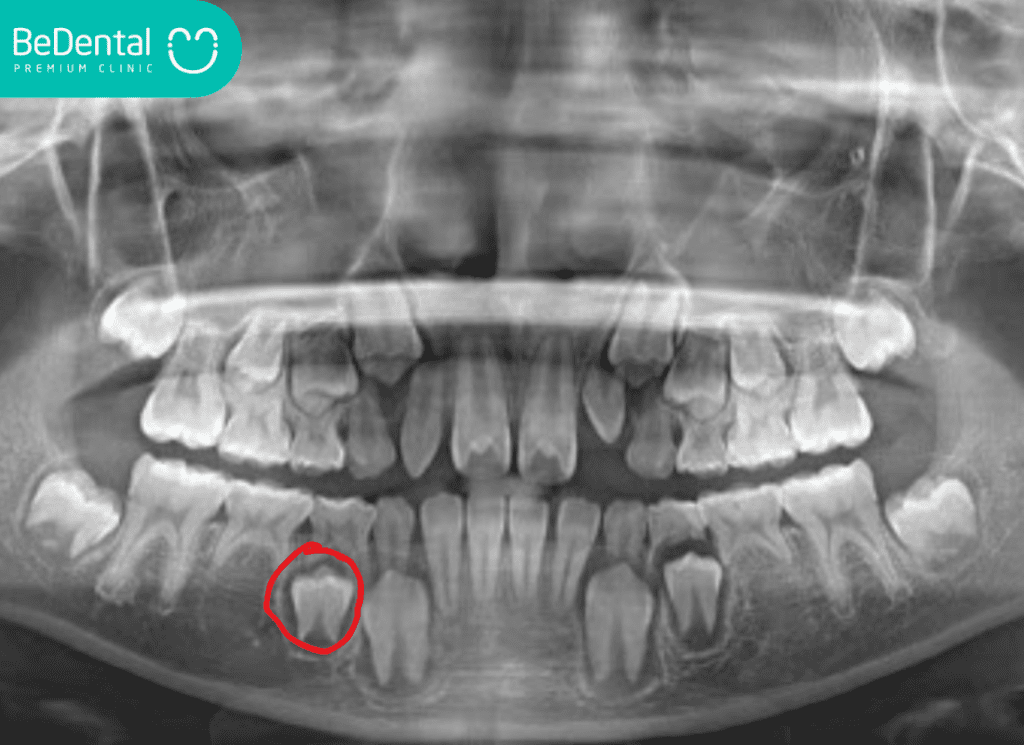

Hiện tượng không có mầm răng vĩnh viễn có thể xảy ra ở bất kỳ vị trí nào, nhưng phổ biến nhất là ở răng cối nhỏ thứ hai hoặc răng cửa bên hàm trên. Việc phát hiện sớm thông qua phim chụp X-quang là yếu tố then chốt để có hướng xử lý kịp thời.

Tại các nha khoa uy tín, quy trình này thường bắt đầu bằng việc thăm khám và chụp phim X-quang để xác định chính xác số lượng mầm răng vĩnh viễn bị thiếu. Dưới đây là bảng giá tham khảo cho các dịch vụ phổ biến nhất hiện nay: